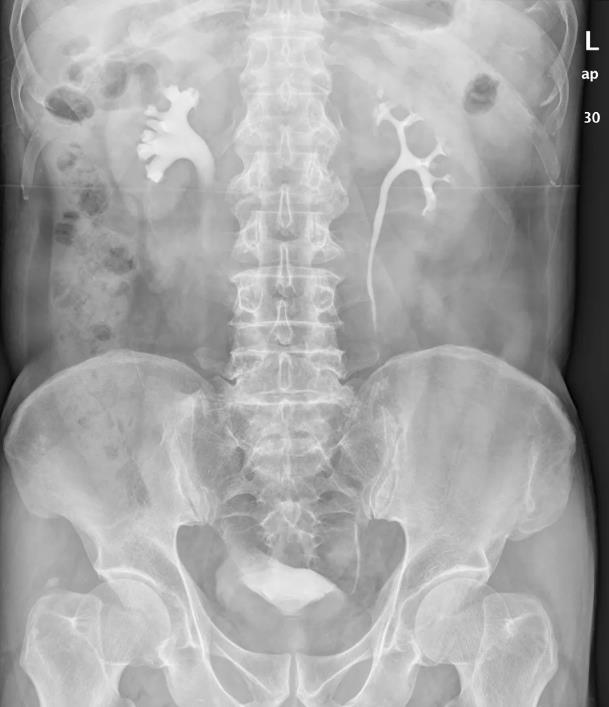

③IVU(靜脈尿路造影):靜脈內(nèi)注射入造影劑,通過(guò)拍攝泌尿系統(tǒng)X線(xiàn)片,可以顯示擴(kuò)張的腎盂腎盞,輕中度腎積水可以顯示腎盂和腎盞擴(kuò)張影,腎功能?chē)?yán)重受損時(shí)和積水量較大時(shí)將會(huì)不顯影。